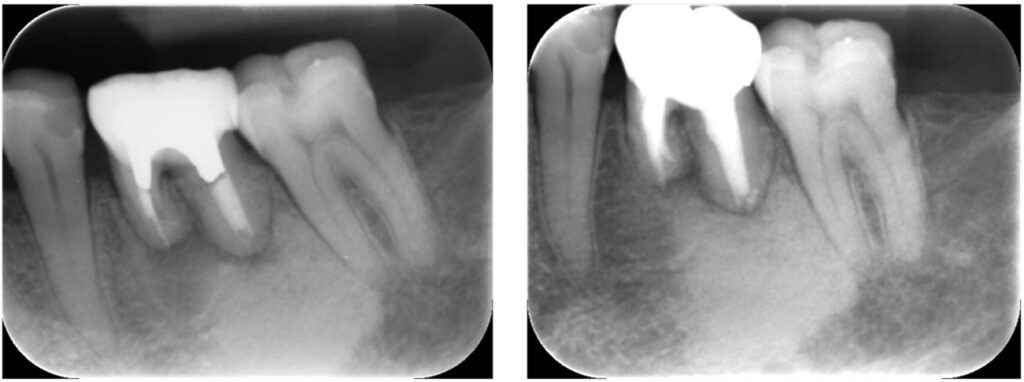

症例25:根尖性歯周炎

激痛で痛み止めも効かない、夜寝れない、顔が腫れている。

50代女性、保険で根管治療した歯を精密根管治療させていただきました。

根尖部の炎症の改善、再感染の防止、審美性の改善を行いました。